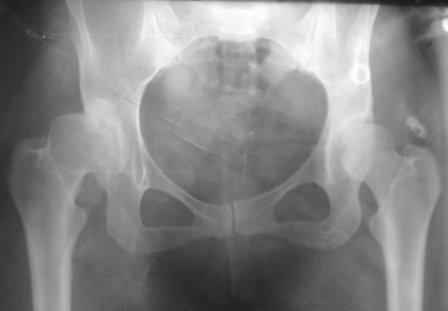

Типичная концовка проигнорированного диспластического состояния сустава. Дисплазия тазобедренного сустава часто встречающаяся патология у жителей Центральной Азии вследствие тугого пеленания в детстве. Традиционно ребенок находится в течение дня в так называемой кроватке "бешик", удобной в быту, но она впоследствии приводит к недоразвитию тазобедренного сустава.

При более сохранном суставе от дальнейшего разрушения можно было бы сохранить только периориентацией нагрузки на сустав - Периацетабулярной Остеотомией .

Данный сустав в начальной стадии разрушения, но все-таки я бы сделал обзорный таз и отдельные снимки сустава в 30 градусной абдукции и аддукции. Также снимки с внутренней и наружной ротацией для оценки состояния головки бедра.